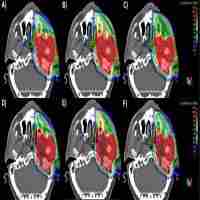

| Abstract | Background Nasopharyngeal adenoid cystic carcinoma (NACC) is a relatively rare salivary gland tumor that is generally associated with poor outcomes. High-dose radiotherapy is a key treatment for patients with NACC. This study reported the long-term efficacy and safety of particle beam radiation therapy (PBRT) for NACC. Methods and materials Twenty-six patients with nonmetastatic NACC who received definitive PBRT alone were included in this retrospective study. The majority of patients (92.3%) had locally advanced disease. Twenty-five (96.15%) patients received intensity-modulated proton radiotherapy (IMPT) followed by a carbon ion radiotherapy (CIRT) boost, and one patient received CIRT alone. Overall survival (OS), local control (LC), regional control (RC), and distant metastasis control (DMC) rates were calculated via the Kaplan-Meier method. Results The median follow-up time was 46.95 months for the entire cohort. Seven patients experienced local recurrence, and one patient experience neck lymph node recurrence. The 3- and 4-year OS, LC, RC, and DMC rates were 100% and 91.7%, 92.3% and 84.6%, 95.8% and 87.8%, and 90.2% and 71.3%, respectively. A total of 91.3% of the patients achieved complete remission of gross tumors at 1 year after PBRT. Severe acute toxicity was observed in only two patients. A grade 4 decrease in visual acuity was observed in one patient with orbital apex invasion. No late grade 3 or 5 toxicity was observed. Conclusion Definitive PBRT provided a satisfactory 4-year OS for patients with locally advanced NACC. The toxicity was acceptable and mild. Further follow-up is necessary to confirm the efficacy and safety of definitive PBRT for patients with NACC. |